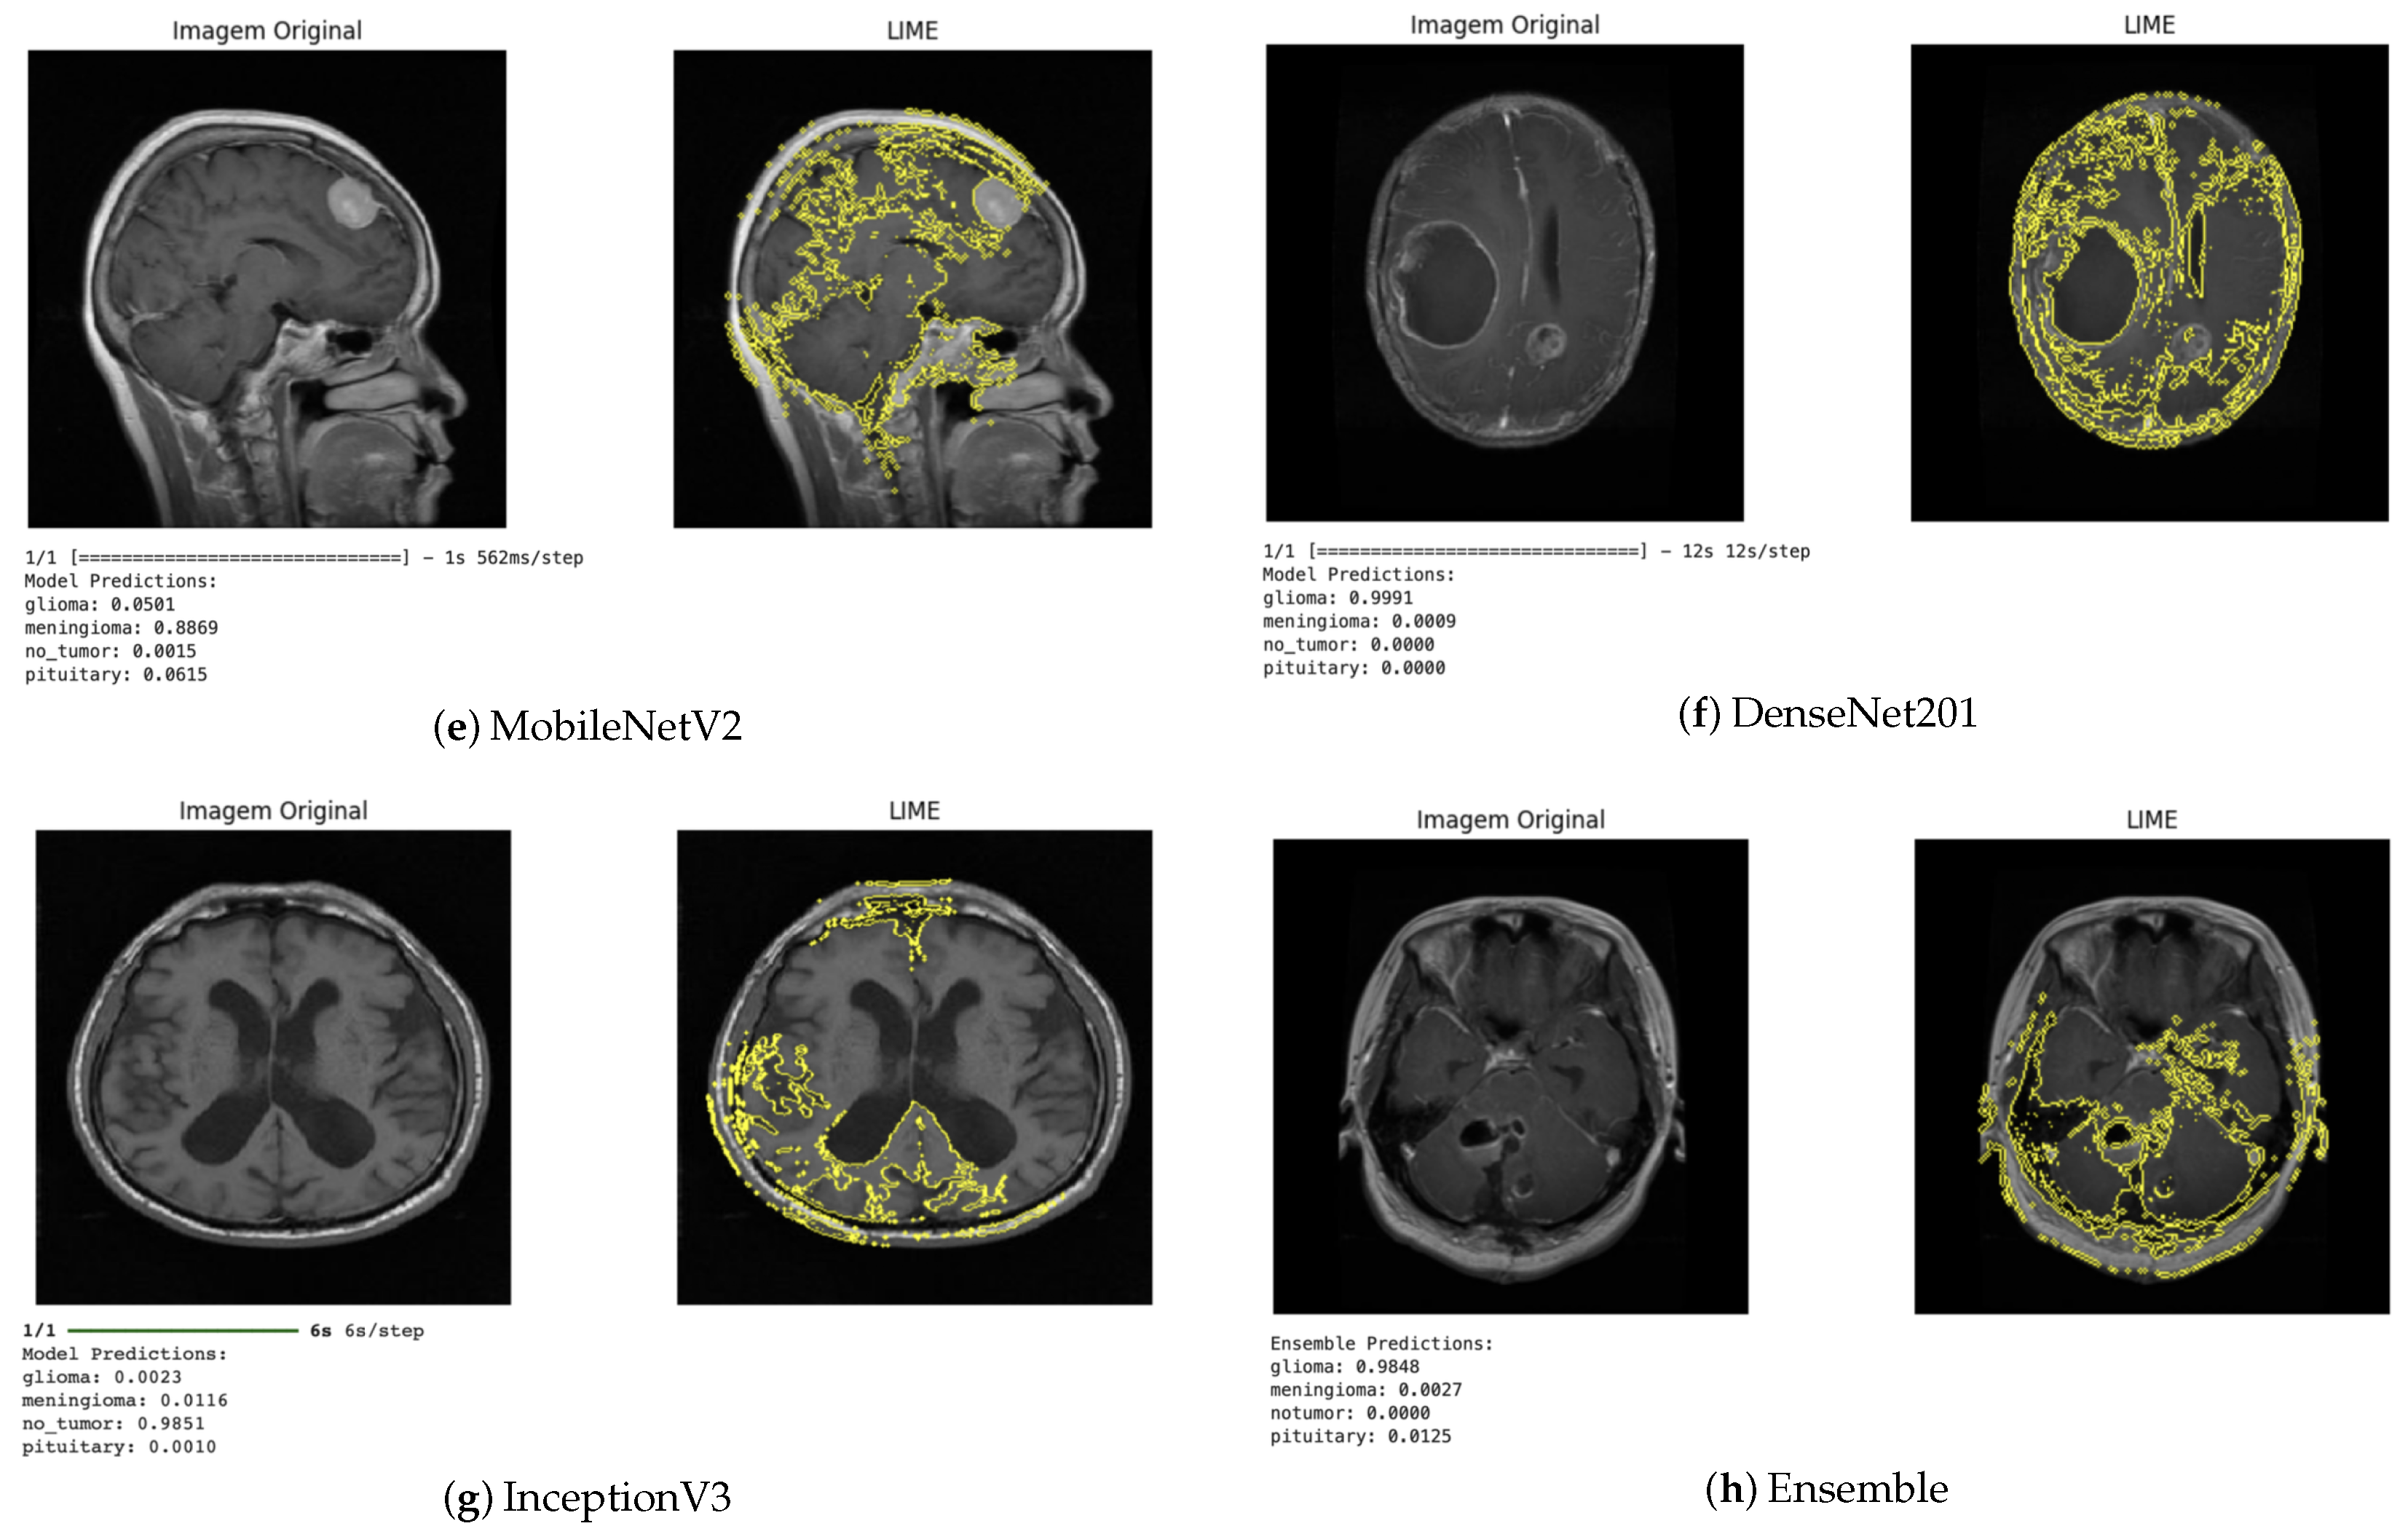

The LIME technique, in turn, provides local explanations by identifying which regions of the image contributed positively or negatively to the classification (Figure 10). This approach enabled a more detailed analysis of the influence of each image segment on the decision-making process. In general, the regions highlighted by LIME showed a high correspondence with those identified by Grad-CAM, reinforcing the consistency of the explanations produced by the different methods.

Figure 10.

LIME visualization for different architectures.